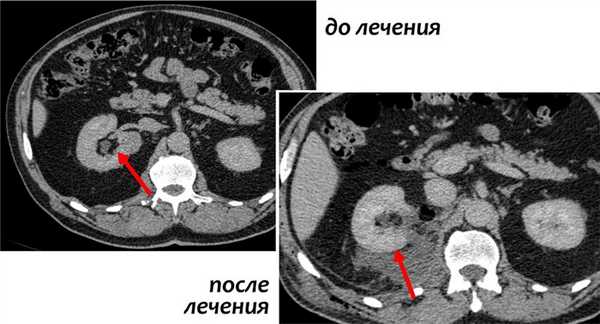

- Таргетная терапия препаратами сорафениб, сунитиниб, сутент, авастин, нексавар позволяет блокировать фактор роста эндотелия сосудов опухоли (VEGF), что приводит к нарушению ангиогенеза, кровоснабжения и роста опухолевой ткани. Иммунотерапия и таргетная терапия при распространенном раке могут назначаться до или после нефрэктомии и резекции метастазов в зависимости от трудноудалимости опухоли и общего состояния здоровья пациента.